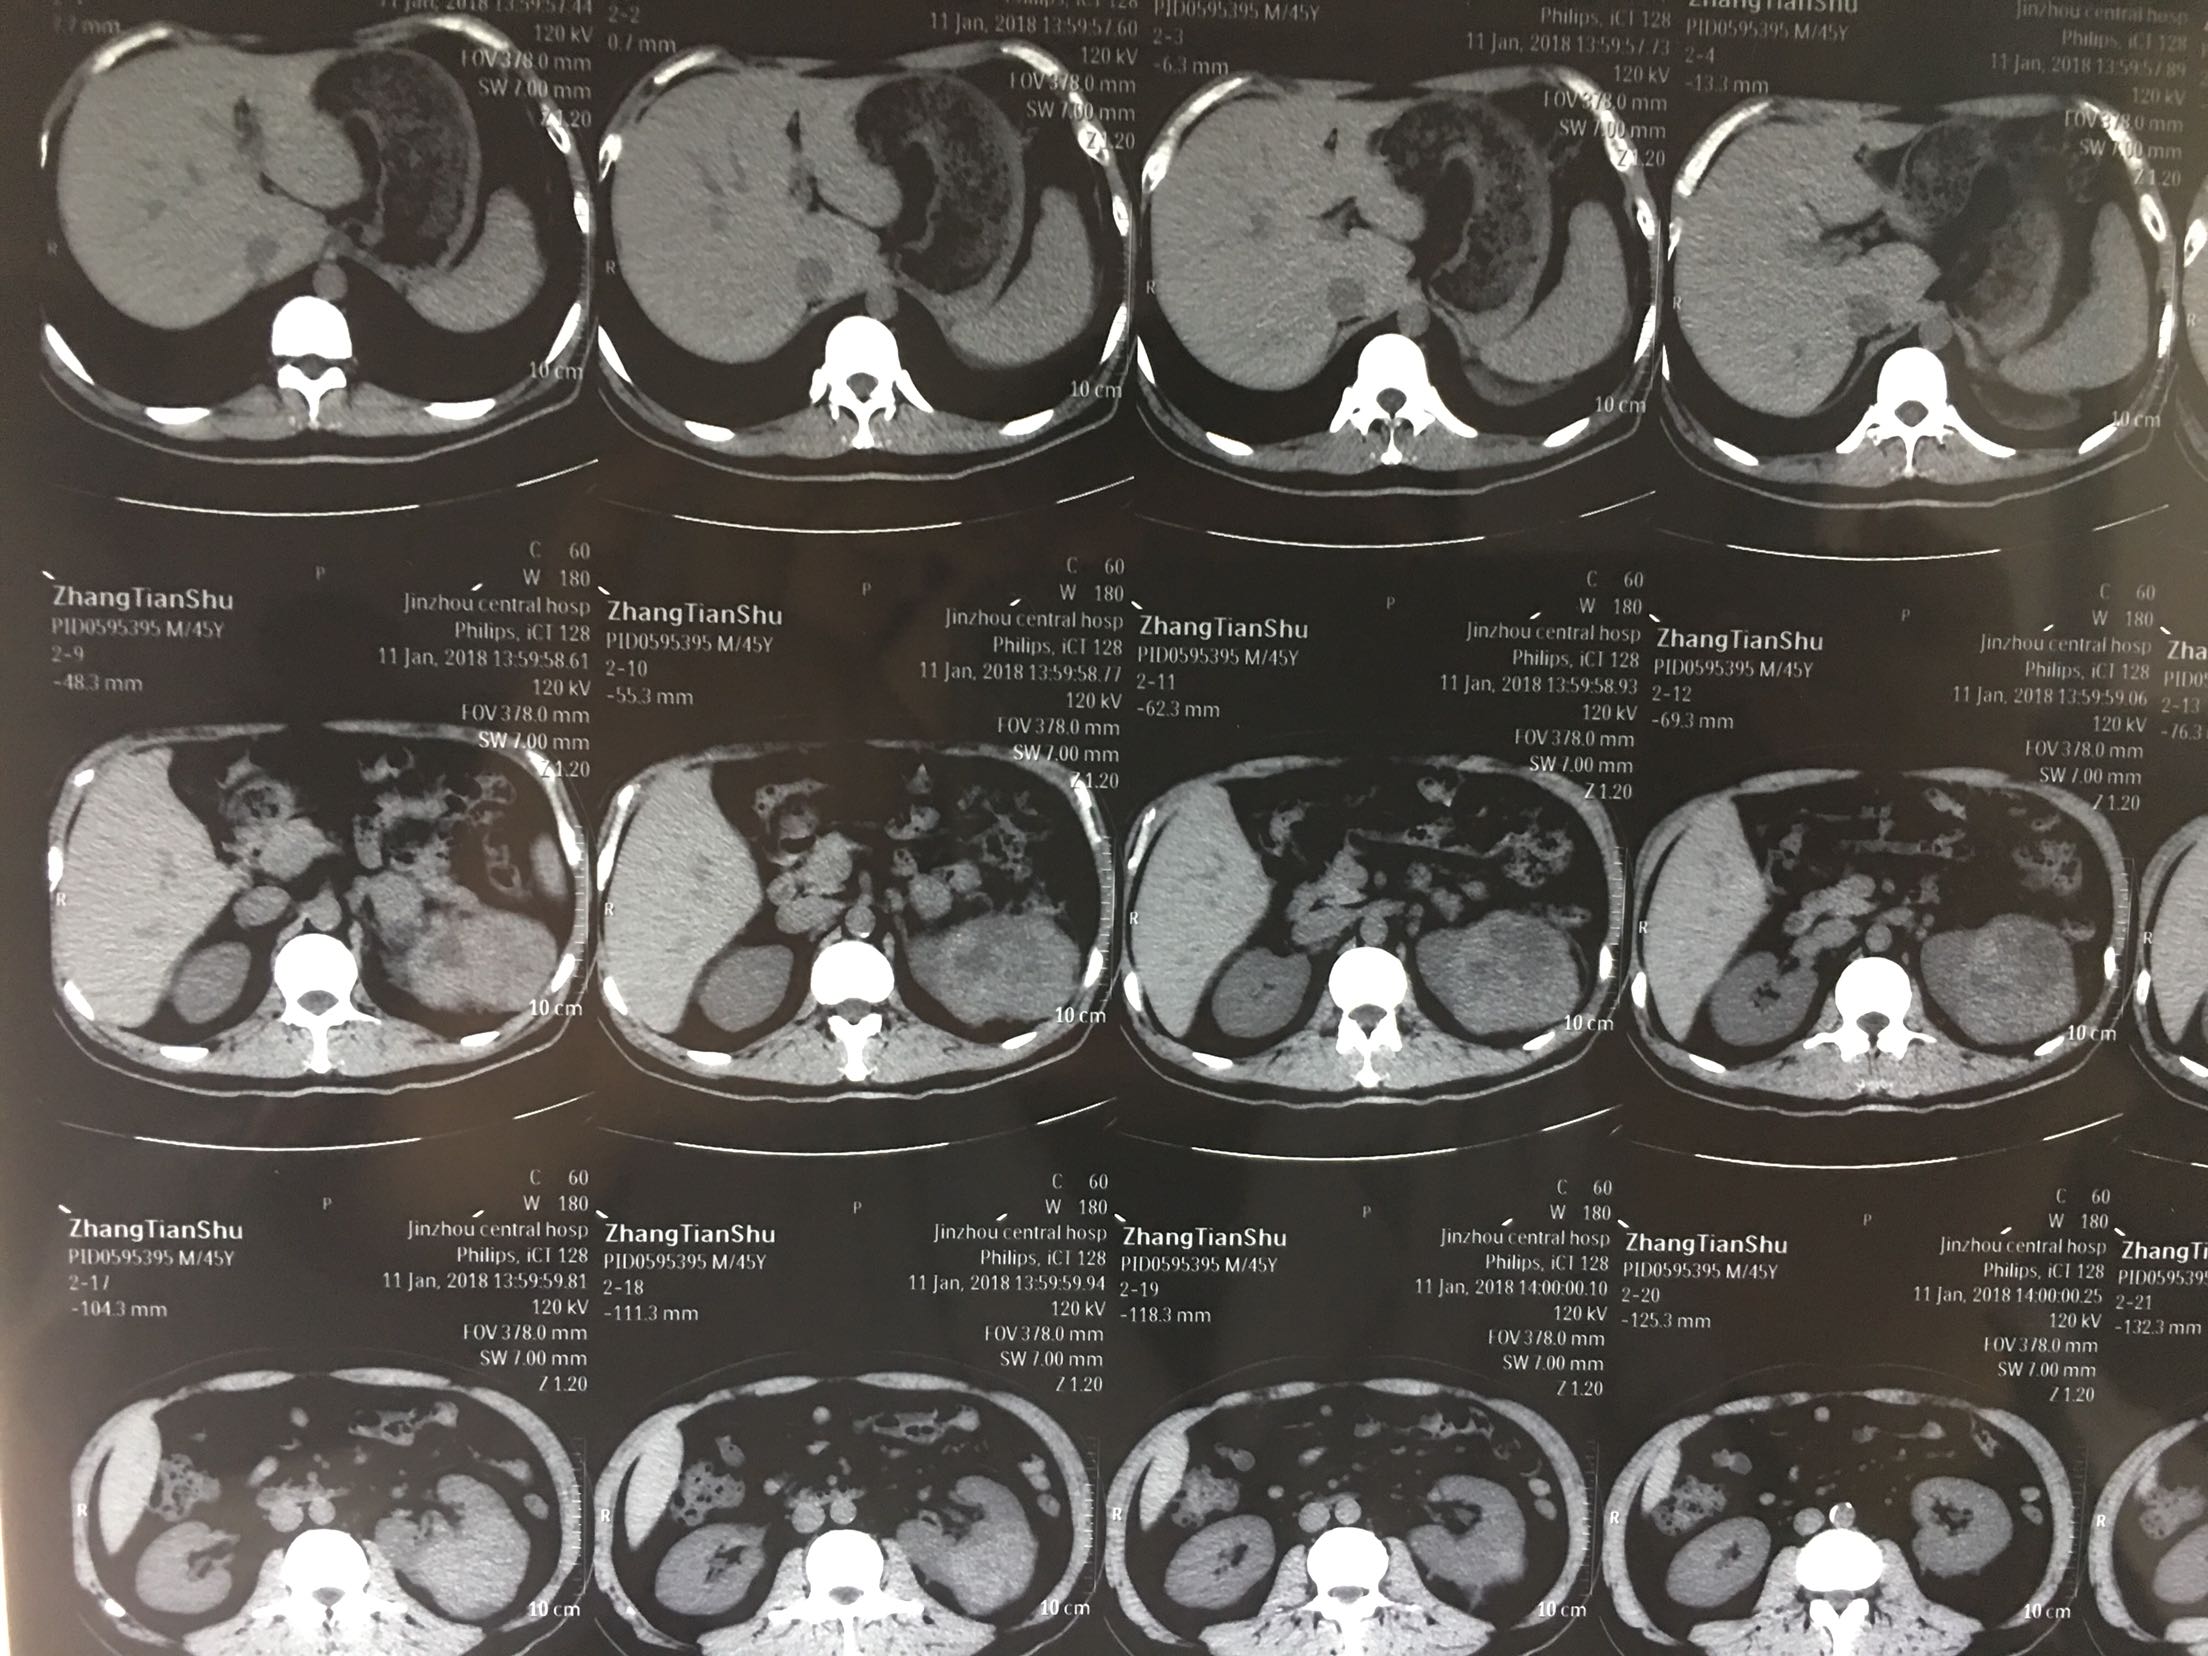

查体:左肾区轻叩击痛,双输尿管走形区无压痛,耻骨上区无隆起及压痛, 辅助检查:泌尿系彩超:左肾肿瘤。 ctu:左肾癌伴同侧肾上腺侵犯。

诊断:左肾癌伴肾上腺转移 治疗:根治性左肾切除术

术后病理:左肾透明细胞癌局部肉瘤样变,肾上腺及腹膜累及。 讨论:肾脏肿瘤肉眼血尿,腰疼,腹部包块为晚期肿瘤症状,预后不良。